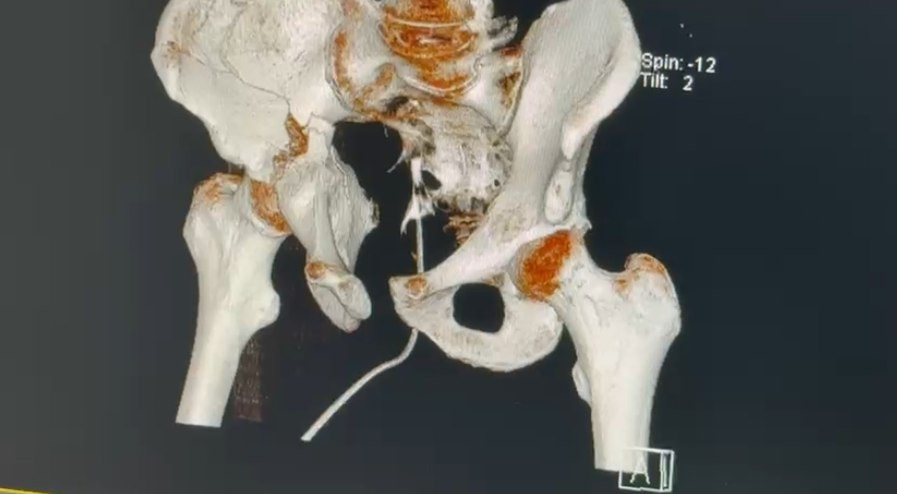

He sustained multiple fractures that required immediate and highly complex surgical treatment. Good news - legs sensitivity is still there. Bad news - he got L4 L5 compression fracture, shattered hip/pelvis and a broken nose. He has already undergone two very complex surgeries for hip reconstruction, one minor nose surgery and now he have to be bed bound for at least 6 weeks under medical supervision.

Hip surgeries were difficult. They required transfering Fedor to a different city to find the only doctor that can do it. A lot of luck that they were a success! But that was not cheap.